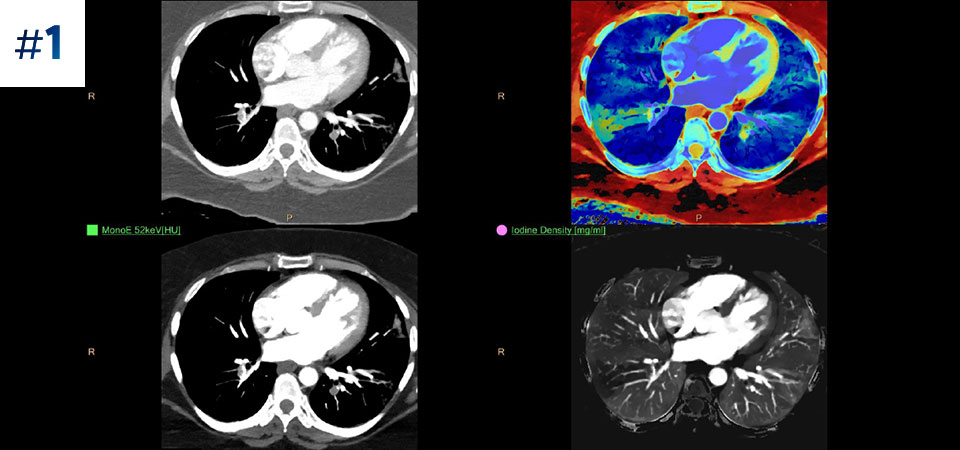

Moins d'examens complémentaires Une meilleure caractérisation et visualisation des tissus contribuent à réduire le besoin d'investigation complémentaire notamment lors de découvertes fortuites.

Allez plus loin que l'imagerie conventionnelle. Constatez par vous-même la pertinence de l'imagerie spectrale à la détection pour améliorer votre confiance diagnostique.

Voir la différence entre le scanner conventionnel et la détection spectrale